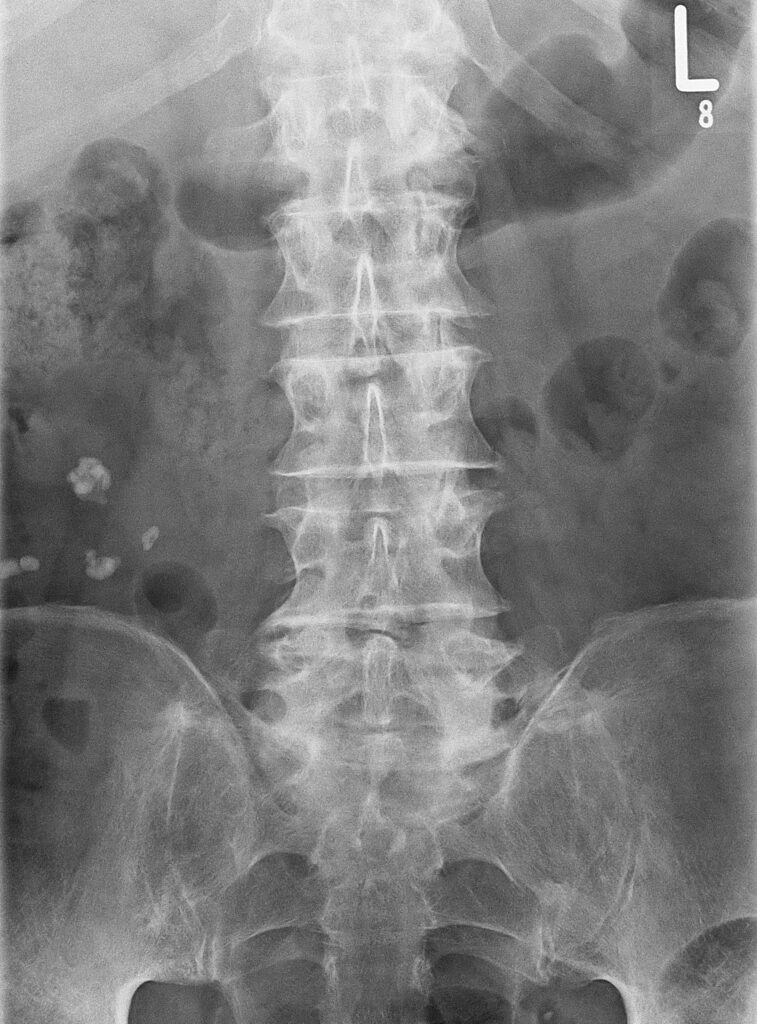

- Darstellen bzw. Einsehen von Knochenbrüchen

- Für die Darstellung von Frakturen oder Verrenkungen und zur Kontrolle während der operativen Einrichtung werden kleine und auf Rollen mobile Durchleuchtungsgeräte durch die Operateure und das Operationspersonal eingesetzt. An den Geräten muss dazu eine operationssterile Verkleidung angebracht werden.